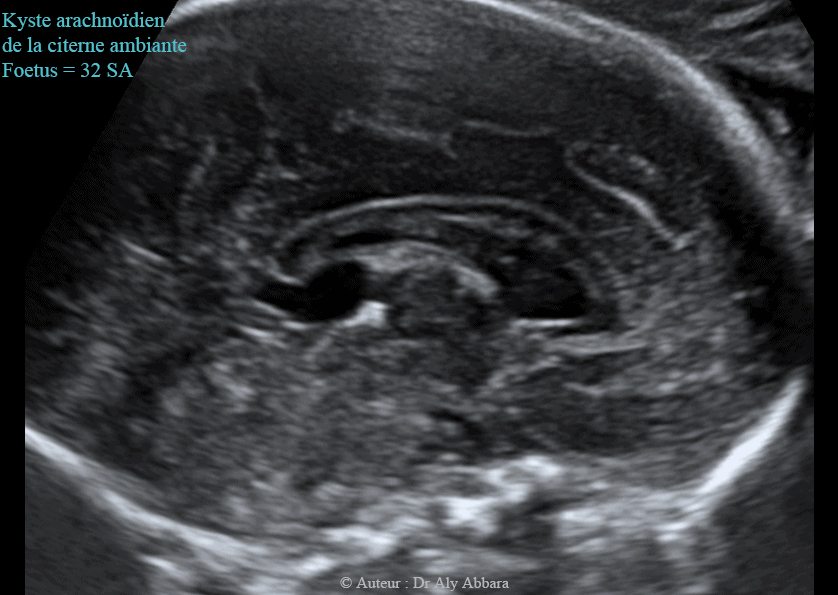

Images échographiques animées montrant la présence d'un probable kyste arachnoïdien cérébral (ou neuroépithélial) évoluant dans la citerne ambiante (en arrière du corps calleux) et mesurant 11 x 18 x 9 mm et associé à une ventriculomégalie bilatérale se caractérisant par l'élargissement des deux carrefours ventriculaires postérieurs qui mesurent 11 - 12 mm de largeur.

Le 3e et le 4e ventricules ne sont pas dilatés.

Il s'agit d'une anomalie isolée chez un foetus de 32 SA; aux échographies du 2e trimestre ce kyste n'était présent.